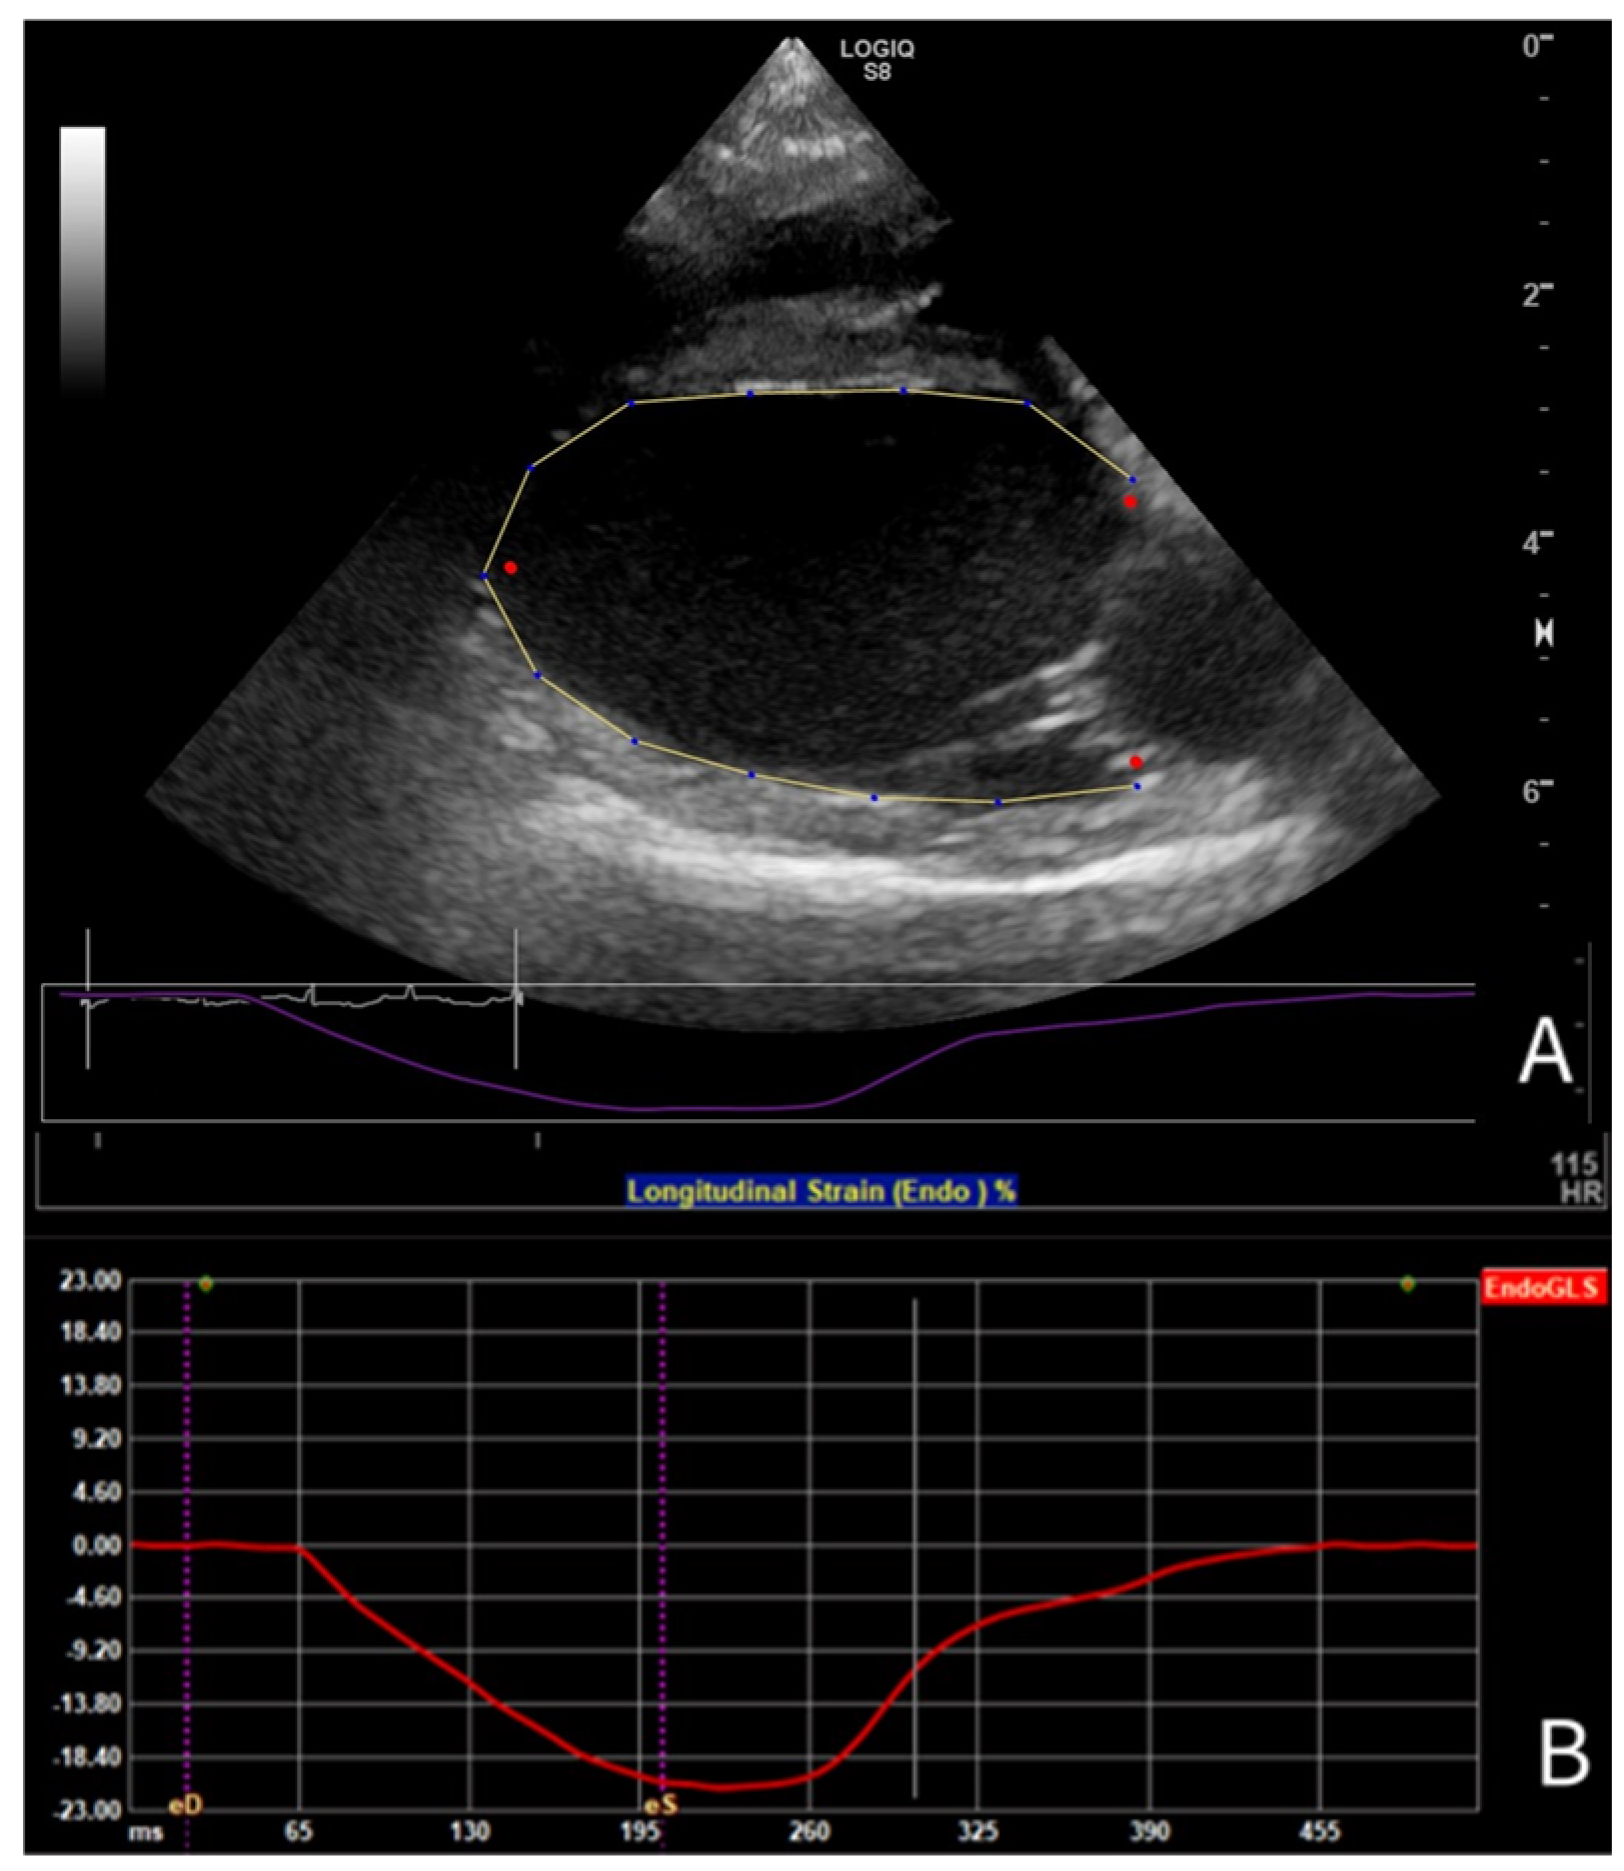

3.2. Results of Strain Analysis